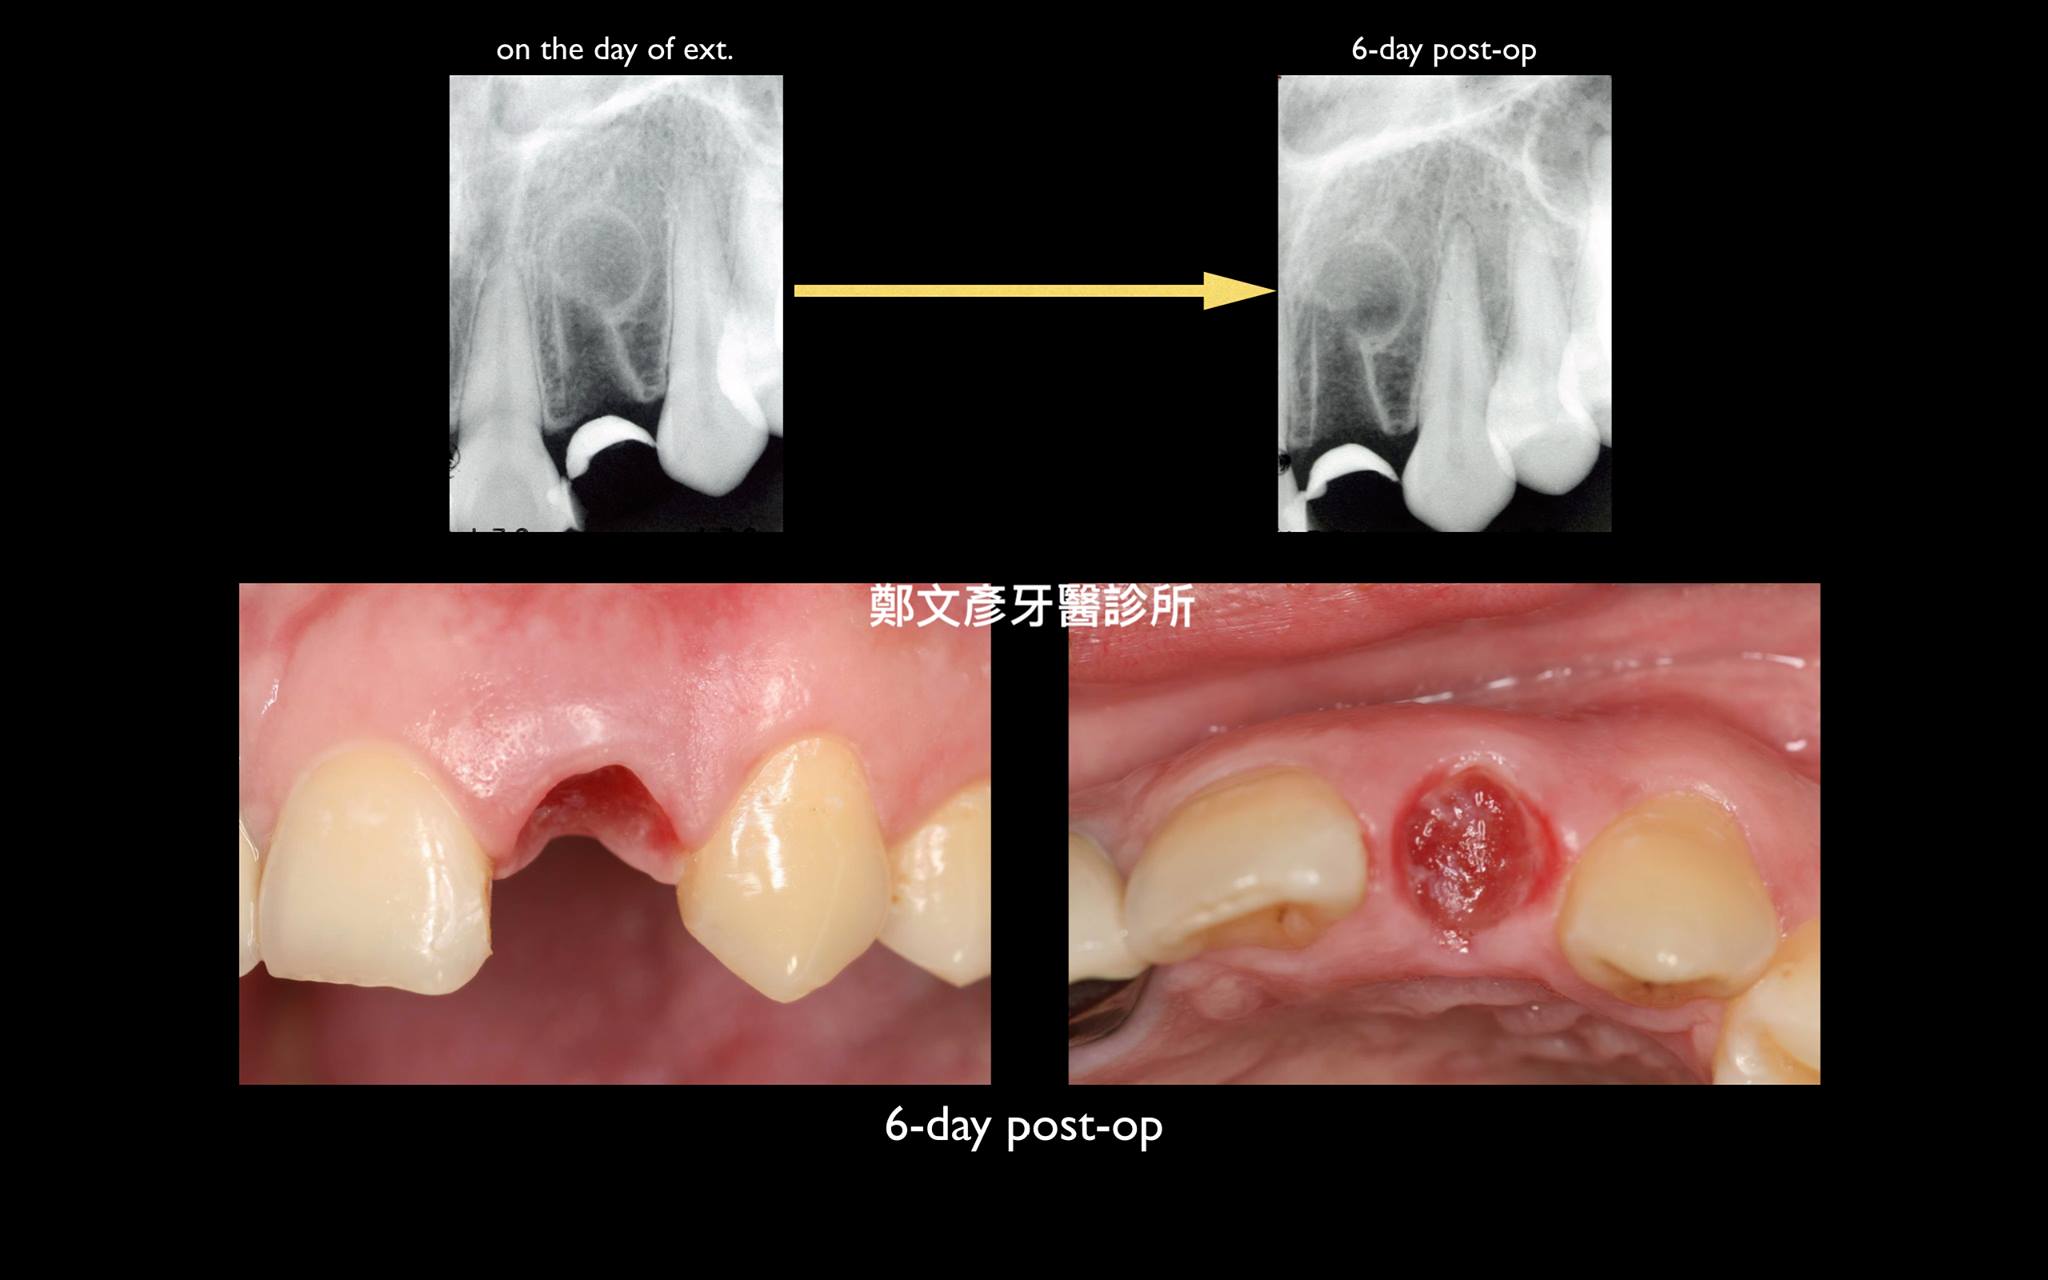

前牙植牙美學及軟組織轉移

Role of granulation tissue in socket preservation